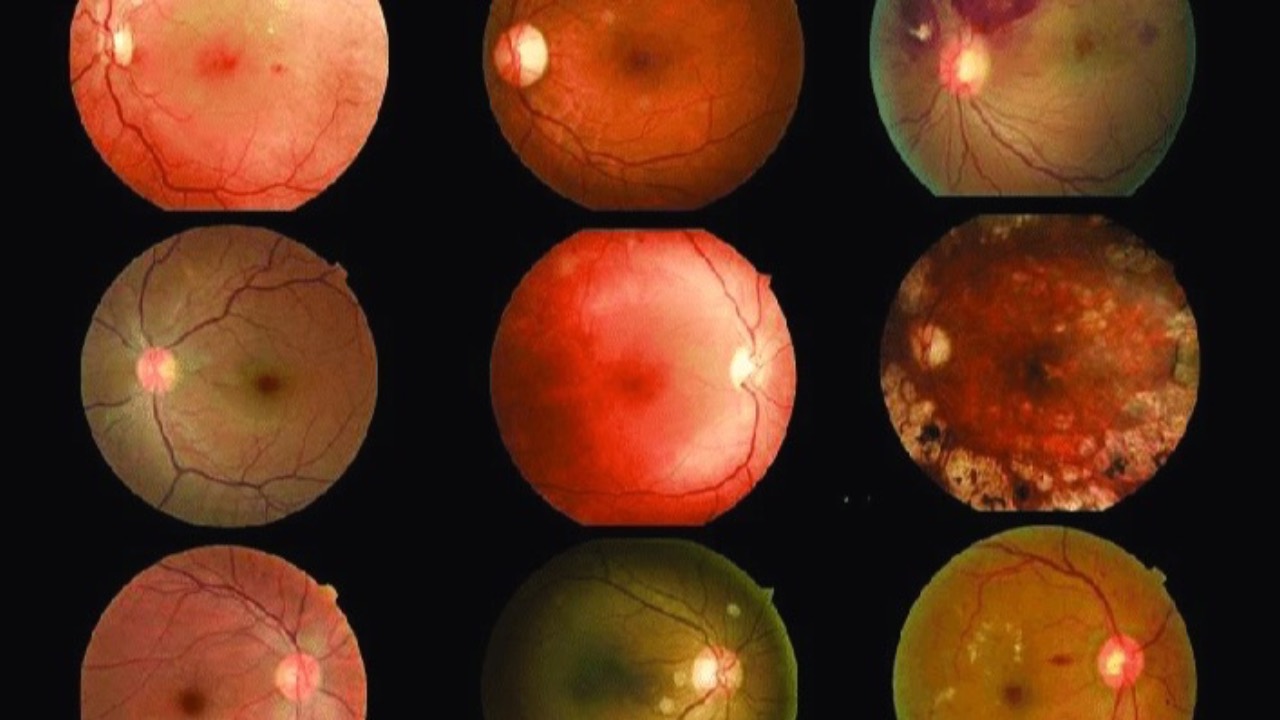

Alcohol & AMD Risk

Another glass of wine...or not?

Recent conclusions from AREDS2 Report 34 gives us some interesting insight into the relationship between alcohol consumption and Age-Related Macular Degeneration (AMD).

The findings revealed a mixed picture, with alcohol's impact varying based on consumption patte...